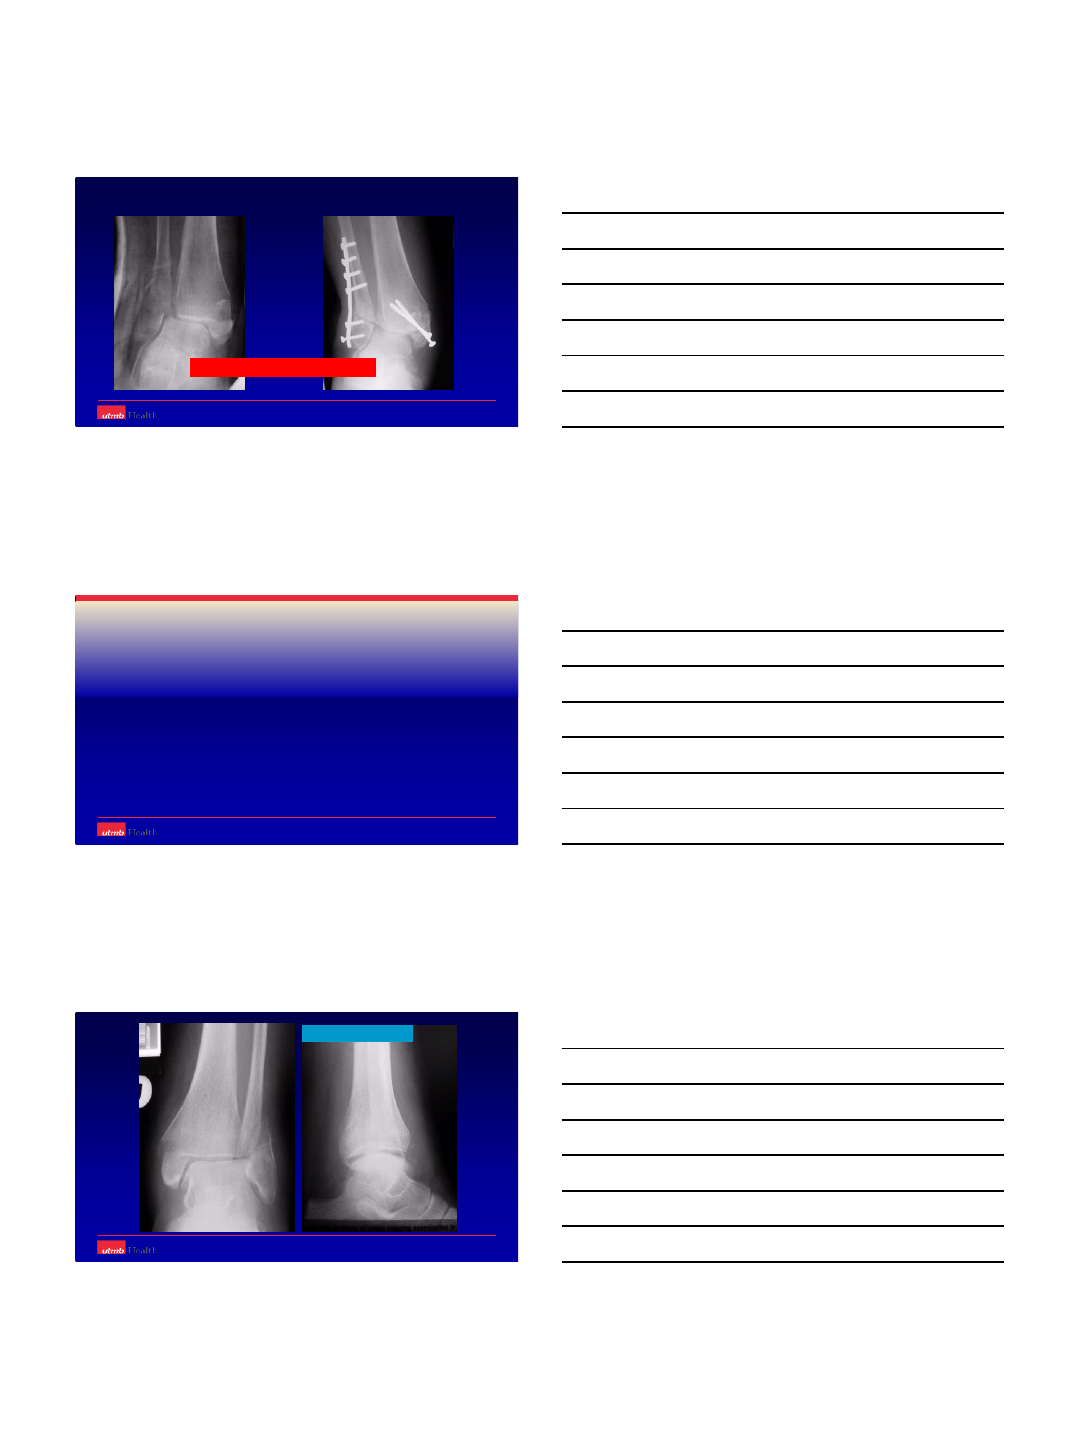

Radiographic Evaluation

-Xrays

3 views [AP/ Mortise/ Lateral view of the

injured and opposite ankle].

Knee xrays if suspicious about maisonneuve

injury.

Failed to Identify

the syndesmotic

Case 3 cont.

Fibular Osteotomy,

Syndesmotic Fusion.